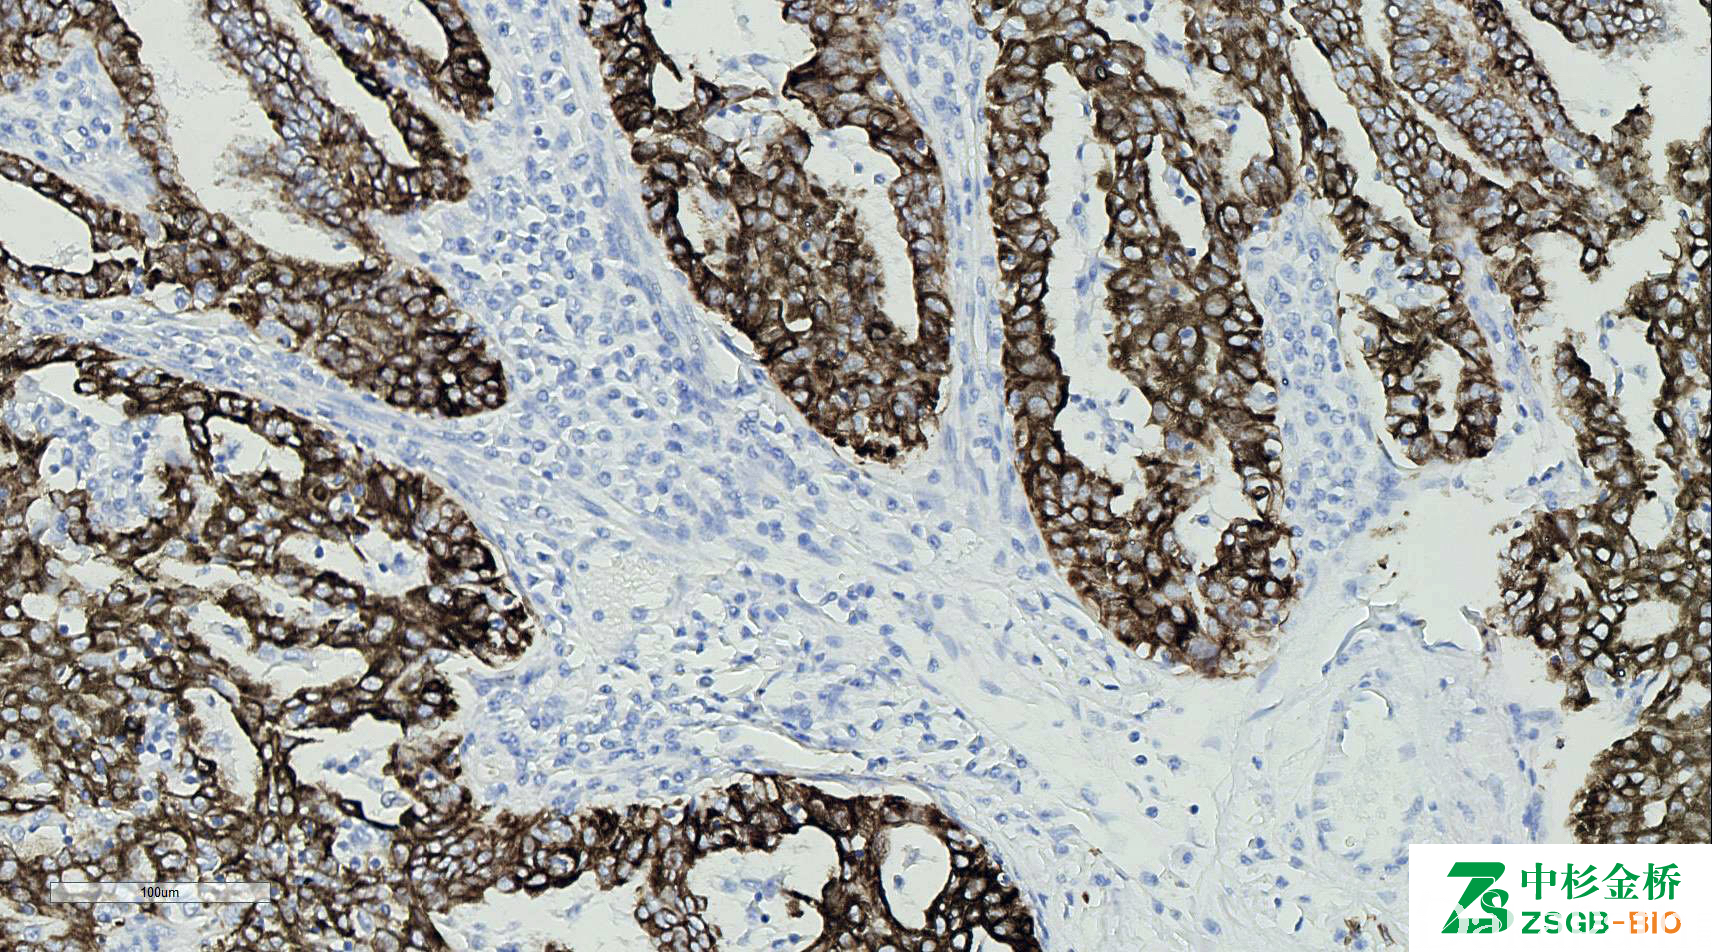

CK19

识别 40kDa 的细胞角蛋白 19,相对分子质量 45000,是分子量最低的角蛋白,与 CK7—起被称为胆管型细胞角蛋白。CK19 对肝细胞不着色,对胆管上皮和肝内胆管细胞癌(ICC)具有特异性染色。

信号定位: 胞质